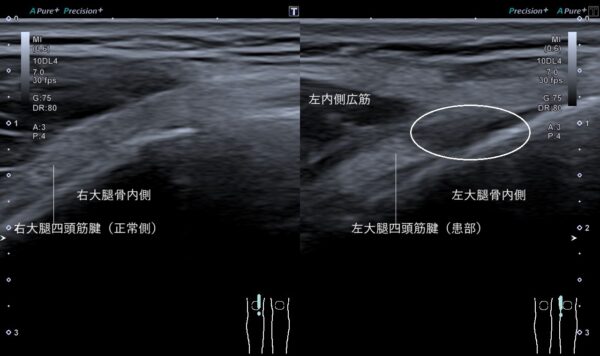

超音波画像観察をすると左大腿四頭筋腱が大腿骨から剥離して損傷していました(画像、丸の中の黒い箇所)。

お皿の骨の周囲は大腿四頭筋腱で覆われていて、その大腿四頭筋腱には太もも前面の筋肉が付着しています。その大腿四頭筋の作用は膝の伸展(伸ばすこと)です。